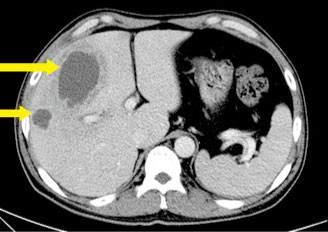

간농양은 간에 생기는 고름집입니다. 세균, 기생충, 곰팡이 등의 감염으로 인해 발생하며, 급성 또는 만성으로 진행될 수 있습니다. 급성 간농양은 진행되어 심각한 증상을 유발할 수 있고, 만성 간농양은 장기간 지속되며 간 손상을 유발할 수 있습니다.